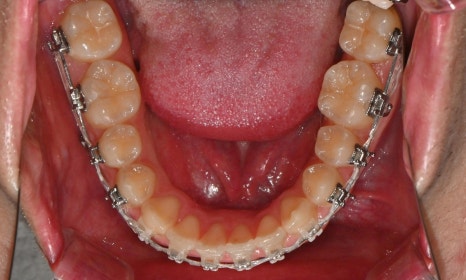

2026.1. 치료 종료 - 연세정원치과

약 1년 간의 교정 치료를 통해 어긋나 있던 치아 중심선이 자연스럽게 맞춰졌고, 중심선 비대칭이 개선 및 하악 아랫입술 돌출도 눈에 띄게 호전되었습니다. 무엇보다 치료 기간 동안 앞니의 치근 흡수는 추가적인 진행 없이 안정적으로 유지되었습니다.

돌출을 조금 더 개선하는 것을 추천했으나, 환자가 갑자기 군 입대를 하게 되어 현 상태로 치료를 마무리하기로 하였습니다. 치료 전후 치아 위아래 중심선이 일치하며 좌우 어금니 교합도 향상되었습니다. 하악 치열의 후방 이동으로 아래 입술의 돌출도도 많이 개선되었습니다. 멀리서도 믿고 내원해주고, 치료 기간 동안 성실히 협조해준 환자분께 감사드리며 앞으로도 건강한 치아로 군 생활 잘 마치길 응원합니다 :)